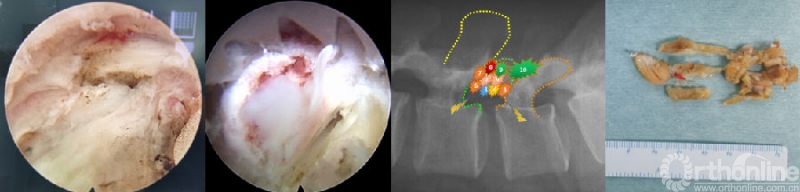

(9)椎间盘准备与终板处理

神经减压充分后,术野电凝止血,充分显露椎间隙后外侧,U套管向内适当牵开硬膜及神经根,T套管向外牵开软组织,用蓝钳或弧形骨凿锐性剪开纤维环至上下软骨终板,大小髓核钳预处理椎间盘组织,显露椎体上下边缘;对于椎间盘的处理可以采用多种工具,如U-T型双套管组合对软骨终板的旋切,可以在直视下整块切除软骨终板至终板下骨,结合方向的摆动,达到扇形的面积以及前方至前纵韧带,保证植骨面的充足。

目前效率更高的内镜融合处理套装已经成熟使用,如镜内铰刀、镜外铰刀、镜外方凿、镜外偏心刮刀等,均可全程直视完成椎间隙处理;如果椎间隙严重狭窄,还可以在U套管内采用开放手术的6-8号铰刀、椎间隙处理工具等盲视下处理,最后通过内镜来检查处理的效果。操作轻柔,避免损伤终板,是减少椎间融合器下沉、移位的重要环节。另外,行走根及硬膜腹侧的纤维环结构需要部分切除,以便于放置保护行走根的“舌形”工作套管。

(10)植骨与融合器置入

椎间隙处理完毕后,置换根据减压碎骨量决定是否需要同种异体骨或人工骨。置换舌形工作套管,在内镜直视下逆时针旋转,将套管舌形部分插入到行走根腹侧,并轻轻敲击固定。选择合适大小的试模,C臂正侧位透视下确定确定大小及位置满意。将减压骨块修整成合适大小置入椎间隙,并敲实。再次内镜下探查,植骨块无脱落,神经结构被保护良好,确定舌形工作套管位置满意及稳定后,置入合适大小椎间融合器。透视显示矢状位及冠状位各角位置满意。